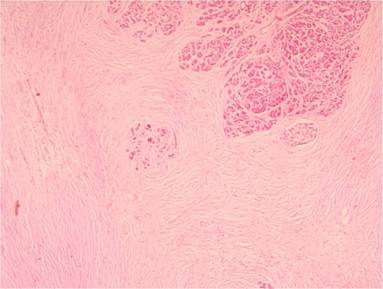

Hematoxylin-eosin stained sections of the specimen showed a highly cellular waving spindle cell proliferation embedded within abundant collagenous and focal myxoid stroma (Figure 3). The spindle cells were running in parallel bundles. Spindle cells were also seen surrounding the acinar cells of the pancreas and proliferating them. The tumor cells showed mild to moderate nuclear pleomorphism with mitotic activity of less than 1 per 10 HPF. No evidence of hemorrhage or necrosis was noted. The tumor was encapsulated and the centre of the tumor also showed pancreatic acinar cells. Immunohistochemical studies showed membranous positivity for epithelial membrane antigen (Figure 4). Stains for CD34 and S-100 protein were negative. In view of the morphology and immunohistochemistry, the diagnosis of perineurioma was made.

Figure 3. H&E staining showing waving spindle cell proliferation embedded within the collagenous and focal myxoid stroma. |